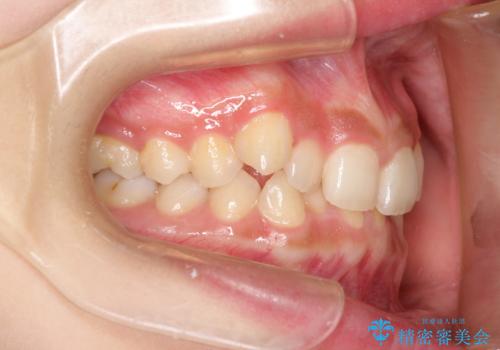

八重歯になっており、下顎の前歯が上顎の前歯に隠れてしまう、ディープバイトという状態でした。

ディープバイトの場合、ワイヤー装置の装着が難しいことがあります。

インビザラインではかみ合わせに左右されず装着できるメリットがあり、ワイヤーに比べインビザラインの方が治療しやすい場合もあります。